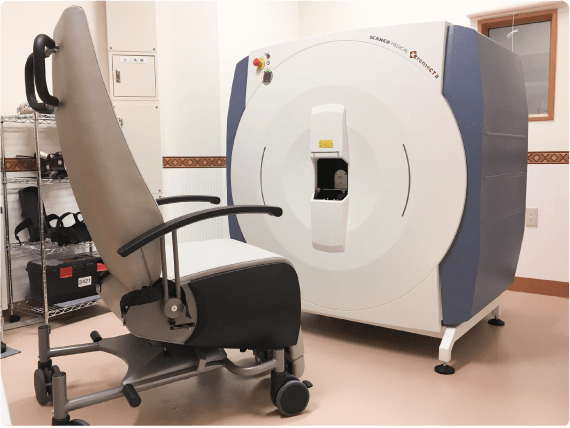

HR-pQCT装置(高解像度の末梢骨用の定量的CT装置)

高解像度末梢骨用定量的CT(high-resolution peripheral quantitative CT:HR-pQCT)は,前腕や下腿の骨を高解像度で撮影し、骨の内部構造を三次元的に評価することができる最先端計測機器です。従来の骨密度検査(DEXA)では評価しきれなかった、「骨の質」や骨の細かい構造の変化を捉えることができ、より高度な骨粗鬆症の診断・治療効果の判定に役立ちます。HR-pQCTは研究機関や専門病院など、限られた施設でしか導入されておらず、先進的な骨の評価を受けられることが当院の強みのひとつです。大学や研究機関とも共同研究を行っています。実際に患者さんの骨の状態を詳しく評価し、テーラーメードの骨の治療を行うようにしています。

脆弱性骨折は繰り返すことが多く、二次性骨折を予防することは極めて重要と考え、骨粗鬆症の治療にも力を入れています。種々の骨代謝マーカーの測定や高解像度末梢骨用定量的コンピュータ断層撮影装置(HR-pQCT)撮影も可能で、骨の微細構造を明らかにし、必要時には実際の治療に取り入れています。多職種(医師、看護師、社会福祉士、薬剤師、管理栄養士、理学療法士、作業療法士、言語聴覚士など)によるチーム医療を積極的に構築し、各職種の専門性を重視した診療を行っています。